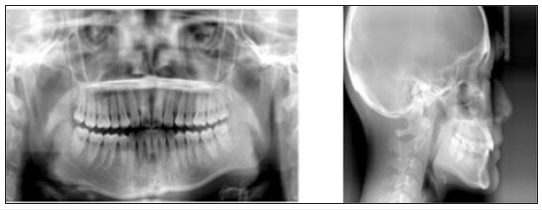

Figure 2:Initial panoramic and cephalometric radiograph.

An 18-year-old female patient presented with a chief complaint of “many spaces over upper teeth and want to close all the space”. The extra-oral examination showed that the chin deviated toward left side for 2mm. The nasolabial angle was slightly acute (90°). An intraoral examination revealed Angle Class I malocclusion with bilateral maxillary lateral incisors missing. The space analysis showed 10mm of space in upper dentition and 1mm space deficiency in lower dentition. Both upper and lower dental arch were symmetric ovoid shape (Figure 1). Cephalometric analysis indicated the facial pattern was skeletal class I malocclusion with proclined mandibular incisors as compared to norms (Figure 2); (Table 1).